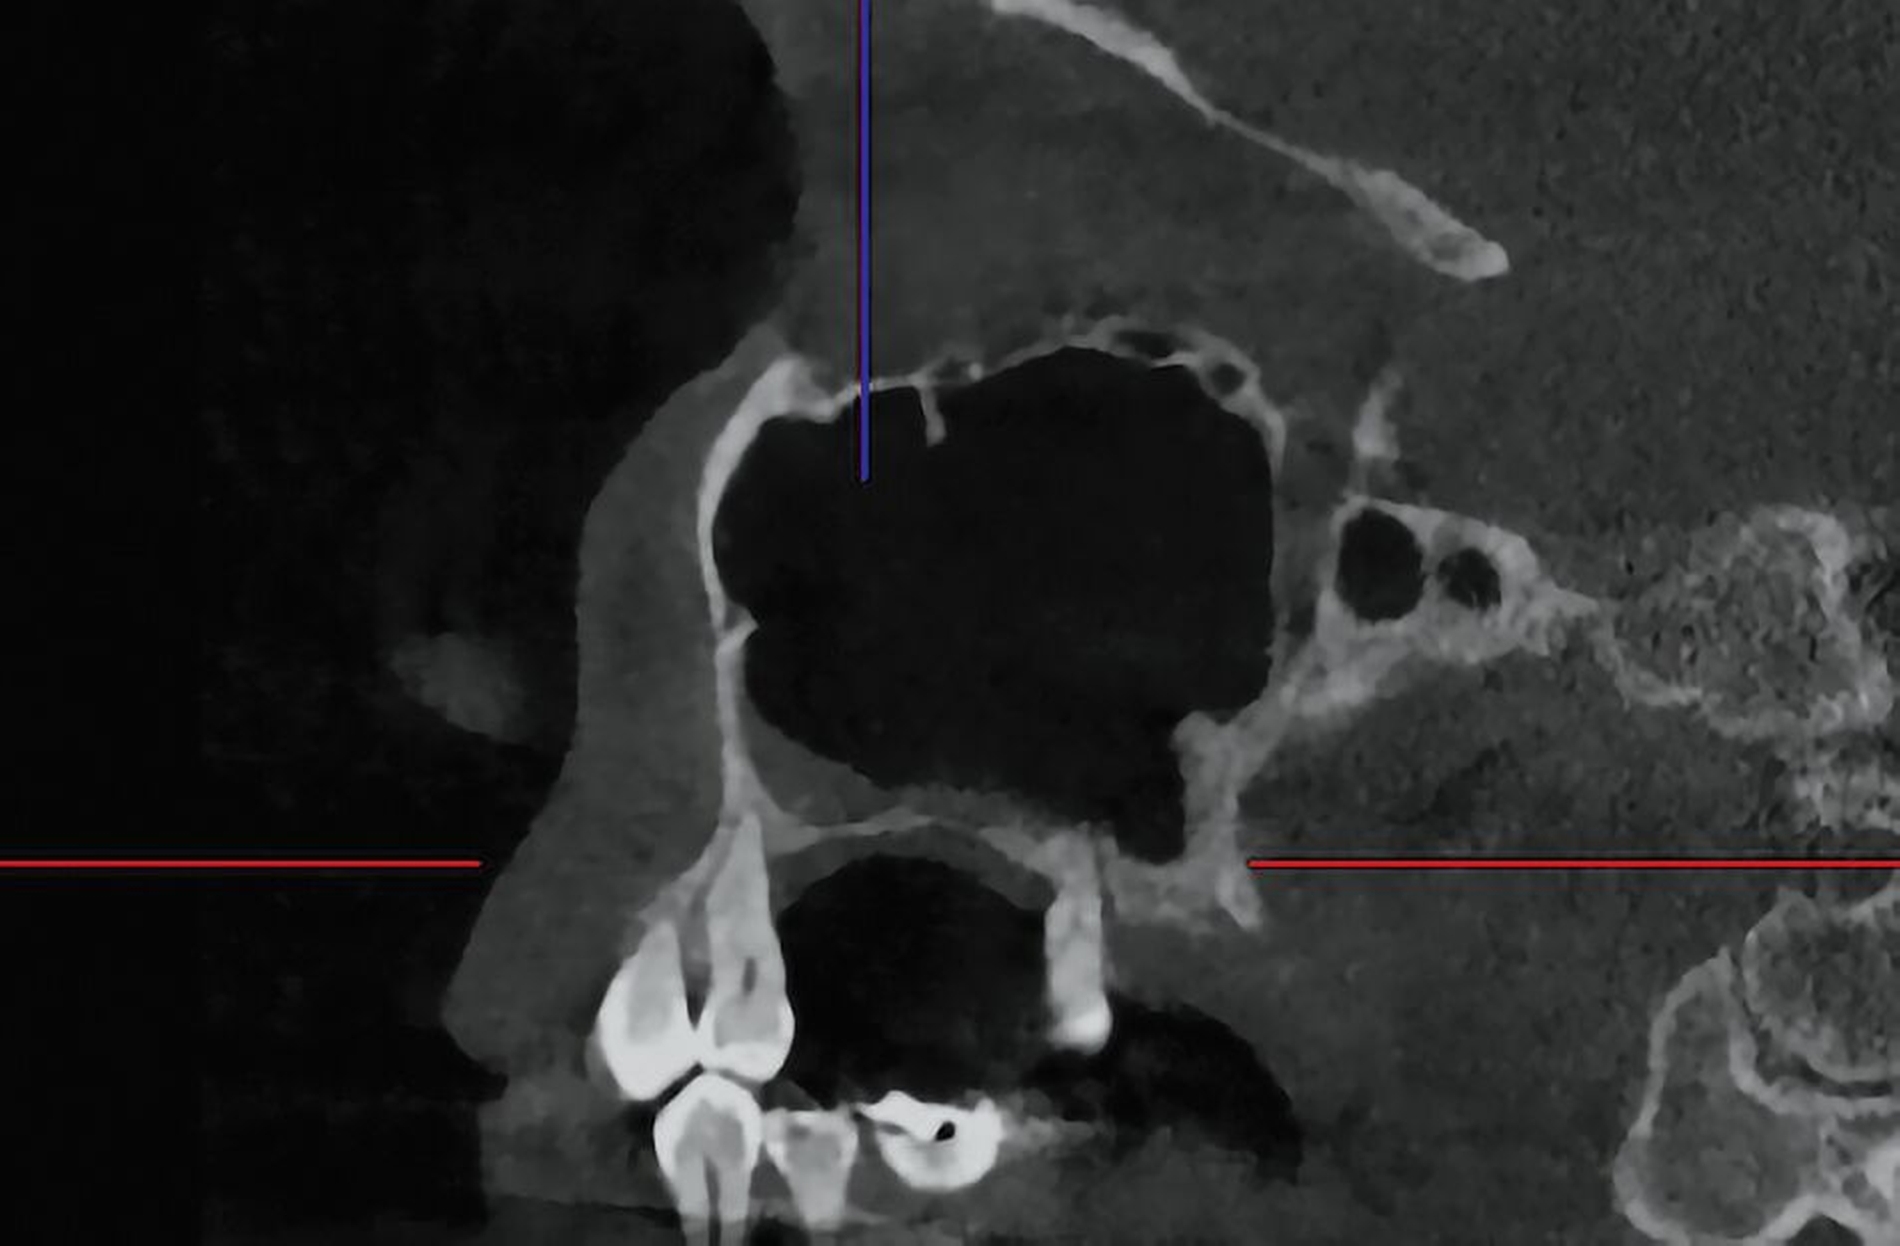

Das DVT zeigte eine Spiegelbildung im rechten Sinus maxillaris, jedoch keinen stark auffälligen knöchernen Befund (Abbildung 2). Die Patientin wurde zu intravenöser Antibiose, Analgesie und Ernährung über eine nasogastrale Sonde stationär aufgenommen. Im Verlauf wurde eine Verbandsplatte per Intraoralscan angefertigt und eine Operation zur Nekrosektomie und Wundanfrischung geplant. Zum Zeitpunkt des operativen Eingriffs hatten sich bereits Teile der vestibulären und der palatinalen Schleimhaut abgelöst. Nach Debridement zeigte sich ein großflächiges Areal mit freiliegendem Knochen. Der Zahn 15 wurde bei Lockerungsgrad III entfernt (Abbildung 3).

Im Verlauf der nächsten vier Wochen zeigte sich keine weitere weichgewebige Granulation (Abbildung 4). Vier Monate nach dem Spülunfall grenzte sich in der DVT-Bildgebung ein Sequester regio 15/16 ab (Abbildung 5), weshalb die Patientin nun zur operativen Sequesterotomie vorbereitet wurde. Der Sequester ließ sich zusammen mit Zahn 16 im operativen Eingriff vollständig und komplikationslos entfernen (Abbildung 6).